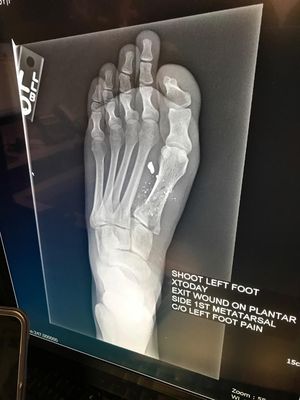

Gunshot Xray

16 year old female accidental gunshot with a 22 gauge rifle

That would be a .22 caliber not a 22 gauge